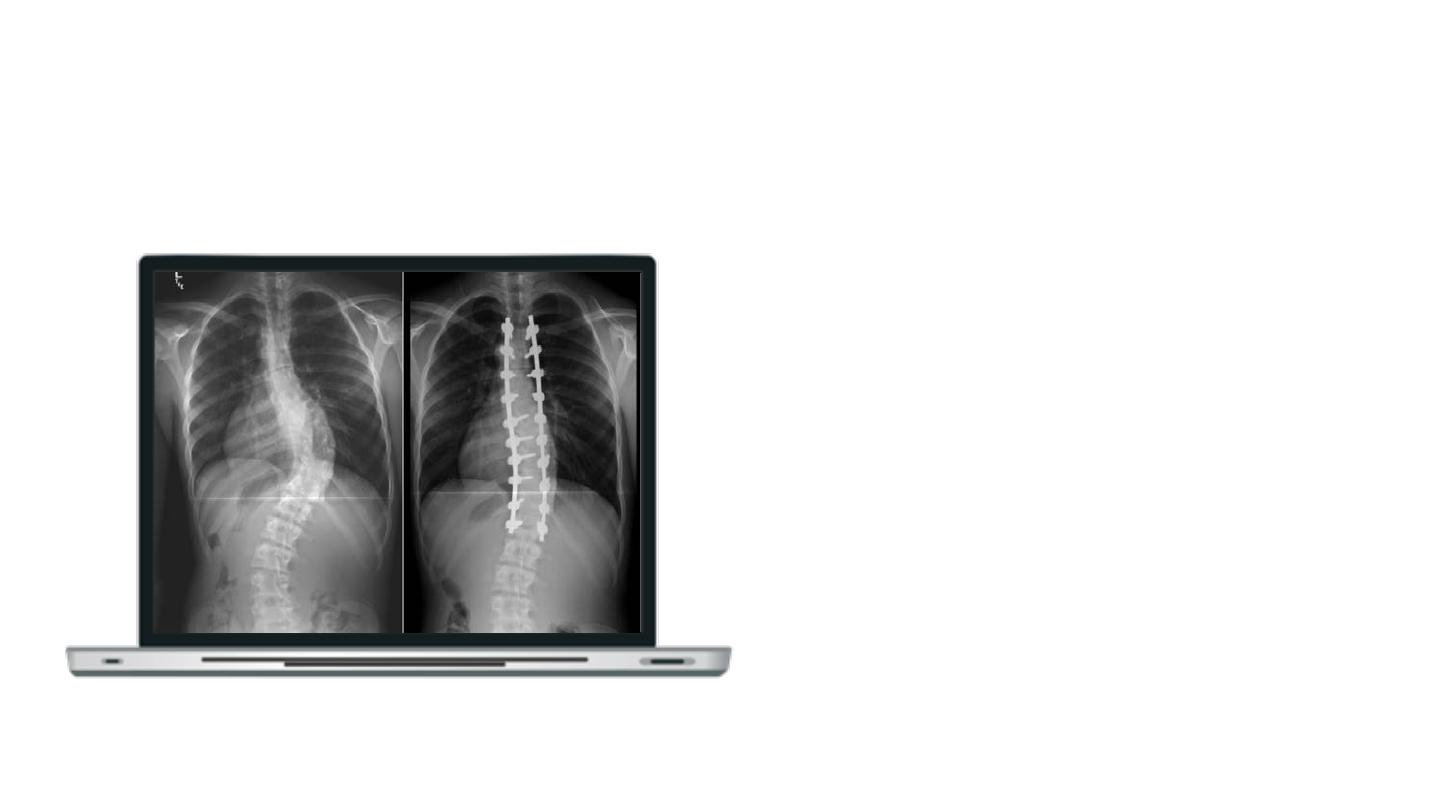

Scoliosis

A medical condition where a person’s spine has a sideways curve.

Adolescent Idiopathic Scoliosis

Scoliotic spine (left) and normal spine (right).